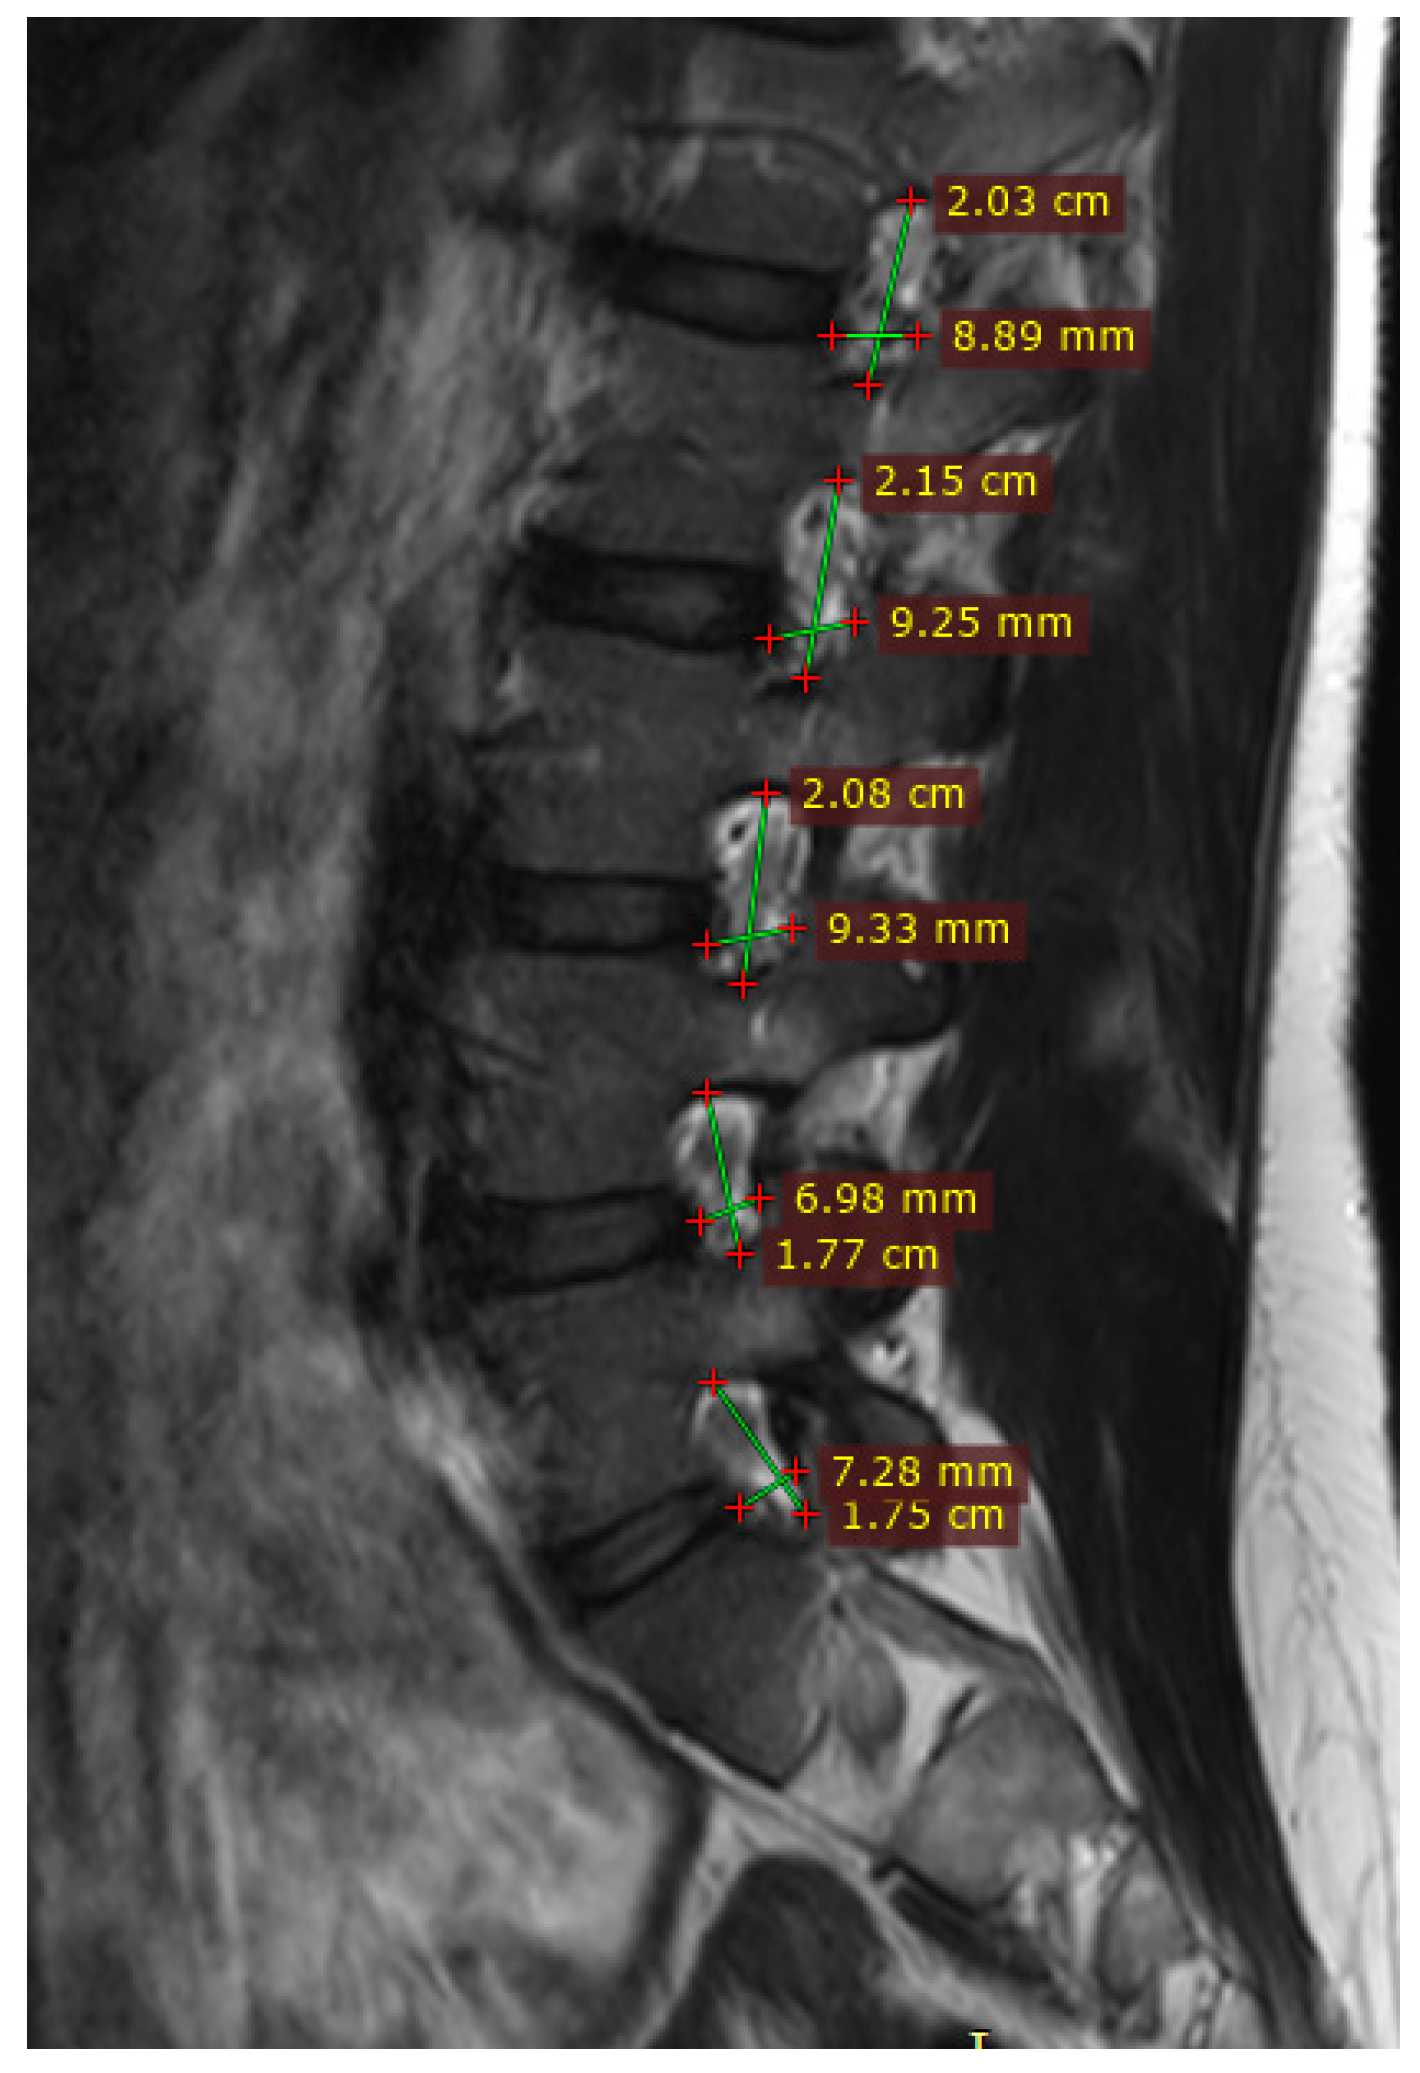

3.1. Volumetric Analysis of Lumbar Foramina